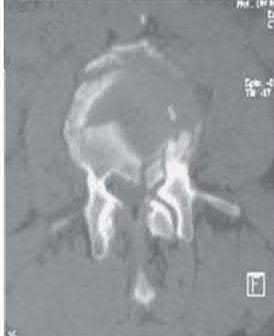

A 45-year-old male is involved in a high-speed motor vehicle collision and presents with the cervical spine radiograph findings typical of traumatic spondylolisthesis of the axis. Which of the following describes the primary mechanism of injury for this specific fracture pattern (Hangman's fracture)?

A 'Hangman's fracture' is a traumatic spondylolisthesis of the axis (C2) involving fractures through the pars interarticularis. The classical mechanism of injury in modern trauma (e.g., unrestrained passenger hitting the windshield) is hyperextension and axial loading. Flexion-distraction typically causes Chance fractures, while flexion-compression typically causes anterior wedge or teardrop fractures.